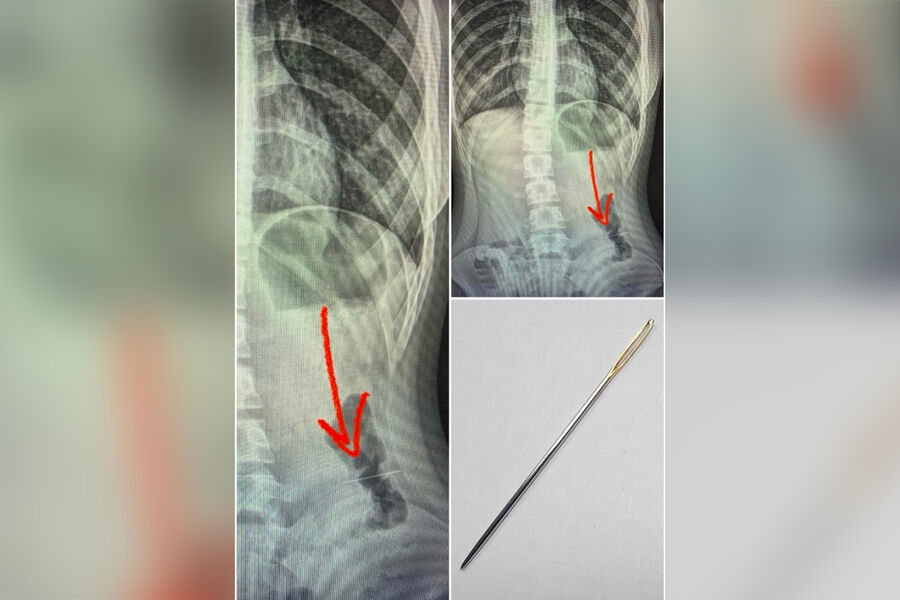

В воронежской областной клинической больнице спасли ребенка, который случайно проглотил иголку во время шитья. Об этом сообщает пресс-служба медицинского учреждения.

Инородное тело попало в пищевод во время изготовления поделки, ребенок занимался рукоделием, держа в этот момент зубами стальную швейную иглу, и в какой-то момент случайно проглотил острый предмет. Пострадавшего доставила в больницу бригада скорой помощи, в ходе обследования врачи обнаружили, что игла застряла в кишечнике.

«Под общим обезболиванием, при проведении диагностической колоноскопии было обнаружено и удалено инородное тело в средней трети нисходящего отдела ободочной кишки», — рассказали в больнице.

Иглу удалось успешно извлечь, жизни и здоровью ребенка ничего не угрожает.